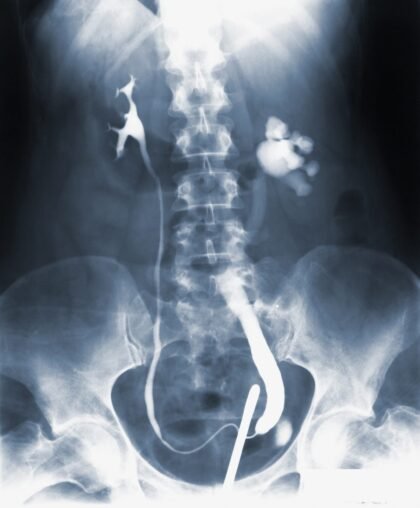

Los síntomas clásicos de la gonorrea son descargas desagradables, dolor en el abdomen y una sensación de ardor al orinar. También puede conllevar otras complicaciones que afectan principalmente a mujeres, como la enfermedad pélvica inflamatoria, embarazo ectópico, infertilidad y una mayor probabilidad de contraer el VIH. No obstante, una persona no siempre exhibirá síntomas, por lo que es posible que padezca la enfermedad sin saberlo.